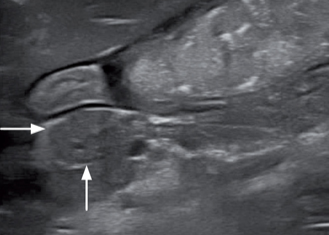

胰腺右支可见的管状结构是胰十二指肠静脉。胰腺左支的管状结构是胰管(图6)。如果不确定,是胰管还是十二指肠静脉,可以使用彩色多普勒去做区分。胰十二指肠有血流信号,而胰管没有血流信号。

胰管作为胰腺分泌功能的总导管,与总胆管共同汇入十二指肠大乳头。十二指肠大乳头在十二指肠壁上呈一高回声小结节,宽度在2.9-5.5mm(图7)。